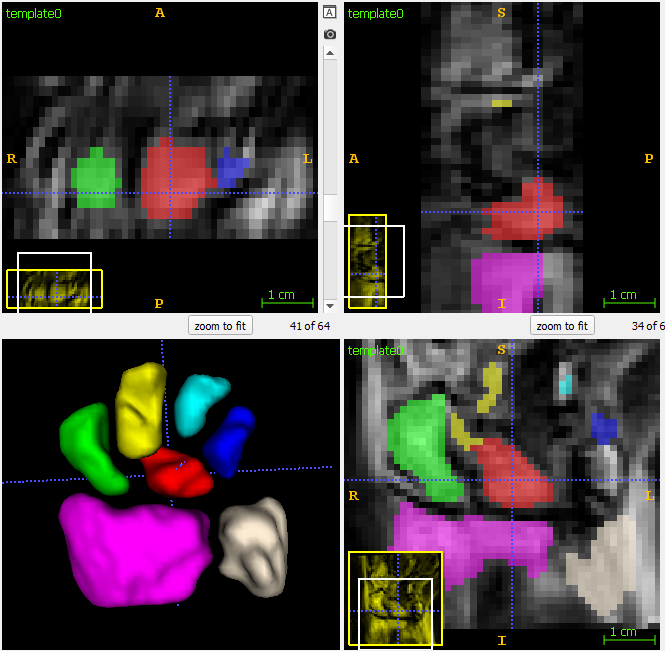

Segmentation of the wrist bones in the template space, which are propagated back to the individual observations via mappings computed during template estimation.

Wrist template seg.png